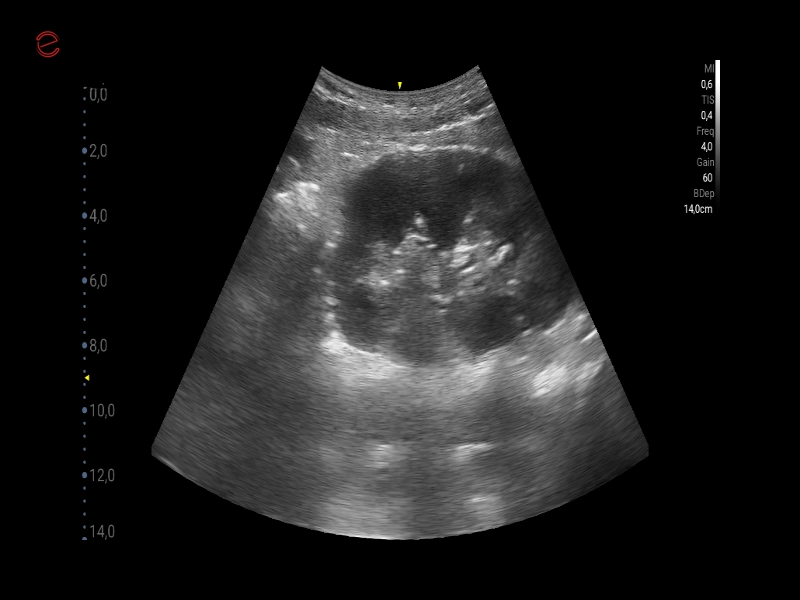

Q7 - GI Kidney

Q7 - GI Kidney

MyLab™X1 Go - GI Kidney

MyLab™X1 Go - GI Kidney

MyLab™X1 Go - Kidney

MyLab™X1 Go - Kidney